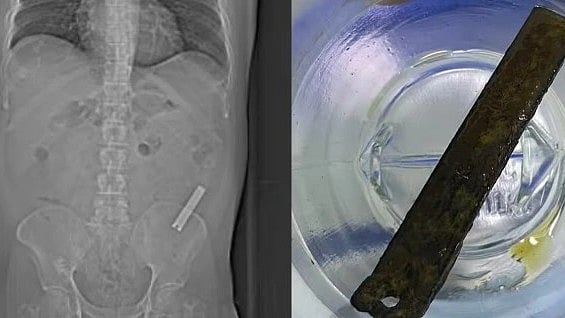

பெங்களூருவை சேர்ந்தவர் ரமேஷ். 38 வயதாகும் இவருக்குத் தொடர்ந்து வயிற்று வலி ஏற்பட்டு அவதிப்பட்டு வந்துள்ளார். இதனால் மணிப்பால் மருத்துவமனைக்கு சிகிச்சைக்காக சென்றுள்ளார்.அப்போது மருத்துவர்கள் எக்ஸ்ரே எடுத்துப் பார்த்துள்ளனர்.

பிறகு 8 வருடங்கள் கழித்து தற்போது வயிற்று வலி ஏற்பட்டு மருத்துவமனைக்குச் சென்று எக்ஸ்ரே எடுத்துப் பார்த்தபோதே உண்மை வெளியே வந்துள்ளது. இதையடுத்து மருத்துவர்கள் அறுவை சிகிச்சை செய்து வயிற்றில் இருந்து நகவெட்டியை வெளியே எடுத்துள்ளனர். தற்போது சிகிச்சைக்குப் பிறகு ரமேஷ் நலமுடன் இருப்பதாக மருத்துவர்கள் தெரிவித்துள்ளனர்.